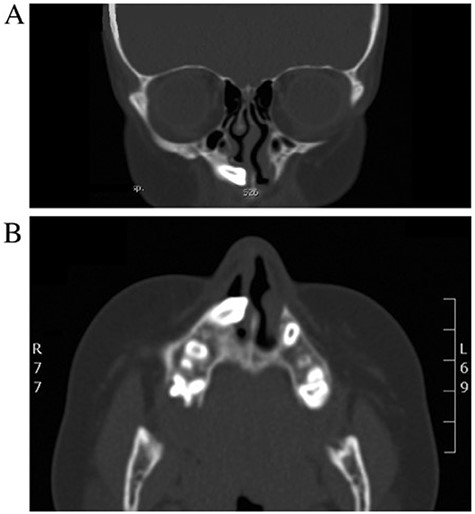

An 11-years-old girl known case of acute lymphocytic leukemia on remission, presented to otolaryngology clinic with right-sided nasal obstruction along with occasional headache. Symptoms are progressive over a period of 1 year. No history of trauma, surgery or foreign body. Examination showed a collapsed right lower lateral cartilage, supratip depression and hard bony mass filling the right nasal cavity. No other remarkable findings. CT of the paranasal sinuses is done and it shows displaced right upper maxillary tooth with crown oriented inferiorly and medially toward and within the lower right anterior nasal cavity with no destruction of the adjacent structures (Fig. 4A and B). Patient was managed with anterior rhinoscopy and endoscopic-guided removal of the ectopic tooth without any complications. The ectopic tooth is found to be canine tooth (Fig. 4). Histopathologic report confirms the diagnosis of ectopic tooth. Post operatively, the patient symptoms improved completely, and she remained symptoms free for 18 months.

(A, B) CT of the paranasal sinuses (coronal and axial view) revealing displaced right upper maxillary tooth with the crown-oriented inferiorly and medially toward and within the lower right anterior nasal cavity.